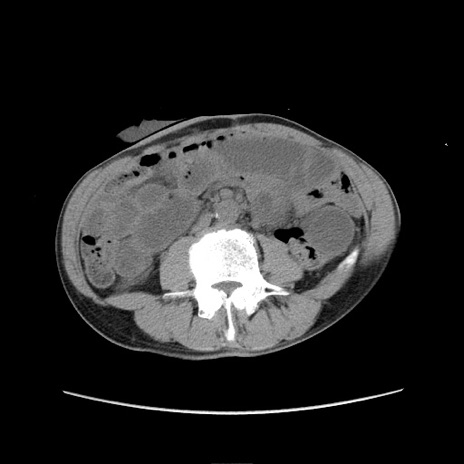

症例11(横断像)

【症例】 60歳代男性

【主訴】 下腹部痛

【現病歴】 本日夜中より下腹部痛の症状認め、受診。

【既往歴】 膀胱癌(膀胱全摘+尿管皮膚瘻術) 、胃癌術後

【身体所見】 BT 35.3℃、PR 58/min、BP 136/98mHg、腹部平坦、軟、腸蠕動音±、ストマ留置あり、左上腹部~正中部に圧痛あり、反跳痛なし。

【データ】WBC 5100、CRP0.01